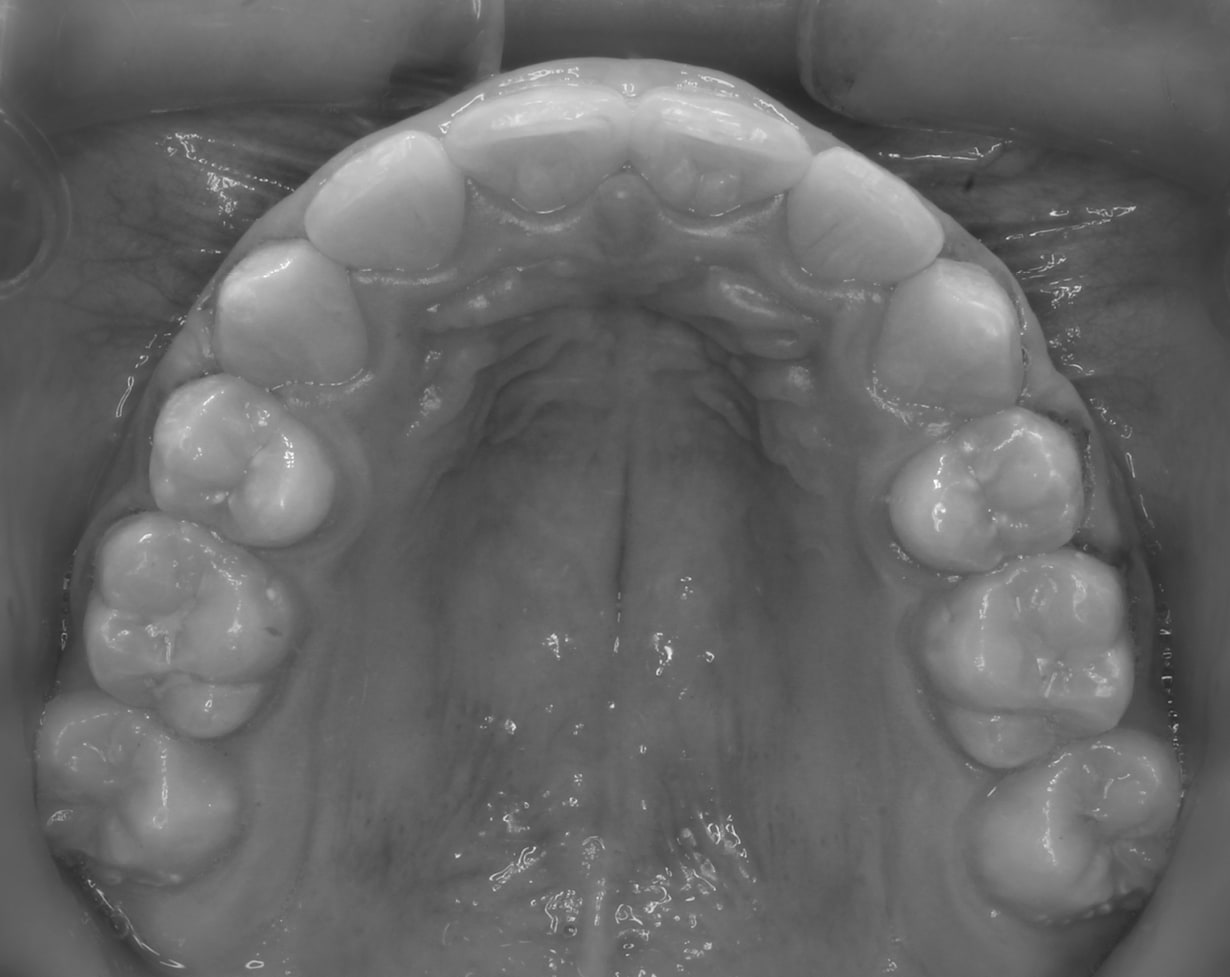

After

Before